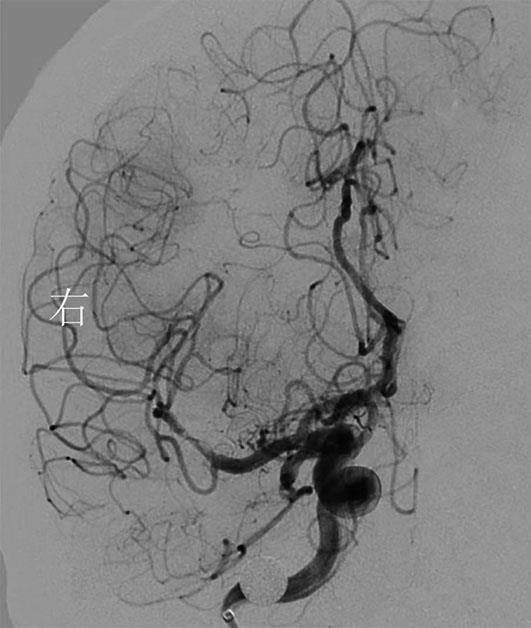

• 挽救性支架植入对取栓困难的脑动脉栓塞开通效果

2022, 47(7):779-783. DOI: 10.13406/j.cnki.cyxb.003067

摘要:目的 探究急性脑栓塞取栓失败和神经介入术中发生医源性脑动脉栓塞后补救性支架植入术的开通效果。方法 回顾性分析2020年1月至2021年11月上海交通大学医学院附属第九人民医院6例脑栓塞取栓失败和4例医源性颅内中远端动脉栓塞、接受补救性支架植入术的患者临床信息,总结患者术后血管开通情况、术后24 h 支架内血流通畅情况、出血转化和预后等情况。结果 6例急性脑栓塞取栓失败,补救性支架植入后闭塞血管全部开通(modified thrombosis in cerebral infarction score,mTICI 2b~3),术后3例出血转化(1例PH2型,2例HI2型),术后24 h支架内血流通畅5例(83%),1例未行血管造影复查;3例患者住院期间死亡。4例医源性中远端动脉闭塞中,1例为原发病为椎基底动脉高度狭窄,支架置入术中发生右侧小脑前下动脉闭塞,补救性支架置入后完全开通,术后24 h复查所有支架通畅,无脑出血,3个月预后良好,改良Rankin量表(modified Rankin score,mRS)评分1分;3例原发病为大脑中动脉栓塞,取栓术中出现同侧大脑前动脉分支闭塞,补救性支架植入后完全开通,其中1例术后24 h头颅计算机体层血管成像(computed tomography angiography,CTA)可见支架通畅,合并片状出血转化(HI2型),2例因为病重未行血管复查。结论 补救性支架植入可以快速开通取栓失败以及医源性中远端动脉的栓塞,但是疗效和安全性需进一步研究。